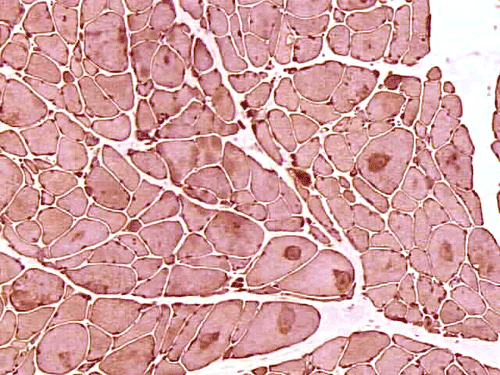

On hematoxylin-eosin stained sections, there is an increased variation of fiber diameter with many atrophic fibers intermingled with fibers of normal caliber. There is no evidence of fiber grouping or perifascicular atrophy. No inflammatory cells are present. There is also mild interstitial fibrosis (Panel A). On higher magnification, many fibers have a round concentric structure (Panel B). Irregular, centrally located depositions are also identified on modified Gomori's trichrome. The concentric nature, however, is not as obvious as in the hematoxin-eosin stained sections (Panel C). Type I and II fibers are not clearly separated in the ATPase preparation at pH 9.4. This is a common situation in chronically ill muscle (Panel D). The type I fibers are unusually dark. There is an increase in the proportion of type I fibers. The atrophic fibers are usually type II fibers. The concentric lesions are found predominantly in type I fibers (Panel E). There is an increase in PAS staining which is consistent with increased glycogen storage (Panel F). No increase in lipid content is demonstrated by oil red O (Panel G). On NADH-TR reaction, the concentric structures appear to have a clear central core that is devoid of enzymatic activity, a rim with intense enzymatic activity and a surround zone with relatively normal reactivity. These features are classic for target fibers (Panel H and I). No deficiency of laminin-2 (merosin) (Panel J) or dystrophin (Panel K) is demonstrated by immunohistochemistry. The central lesions are also immunoreactive for both laminin-2 and dystrophin. Immunohistochemistry for desmin demonstrate a core of strong immunoreactivity and also strong reaction in the sarcoplasmic membrane (Panel L and M). The target structures are also well demonstrated on semithin sections (Panel N). On electron microscopy, z-disc streaming is a common finding and they are often admixed with a substantial amount of dense granular electron dense substance (Panel O and P). There are also numerous cytoplasmic bodies characterized by radiating intermediate filaments (spheroid bodies) (Panel Q and R).